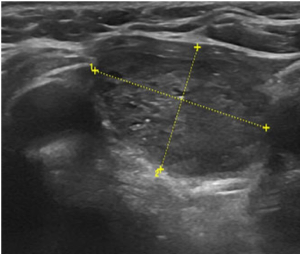

Фотографии и снимки – УЗИ узл

щитовидной железы до проведения

термоабляции и через 6 месяцев